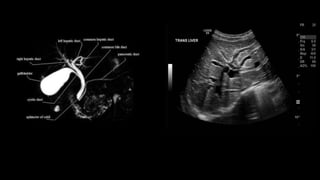

PERCUTANEOUS TRANSHEPATIC

CHOLANGIOGRAPHY (PTC)

Radiographic visualisation of

biliary duct system.

• Ultrasound / CT – assessing the biliary anatomy and cause and level of

obstruction.